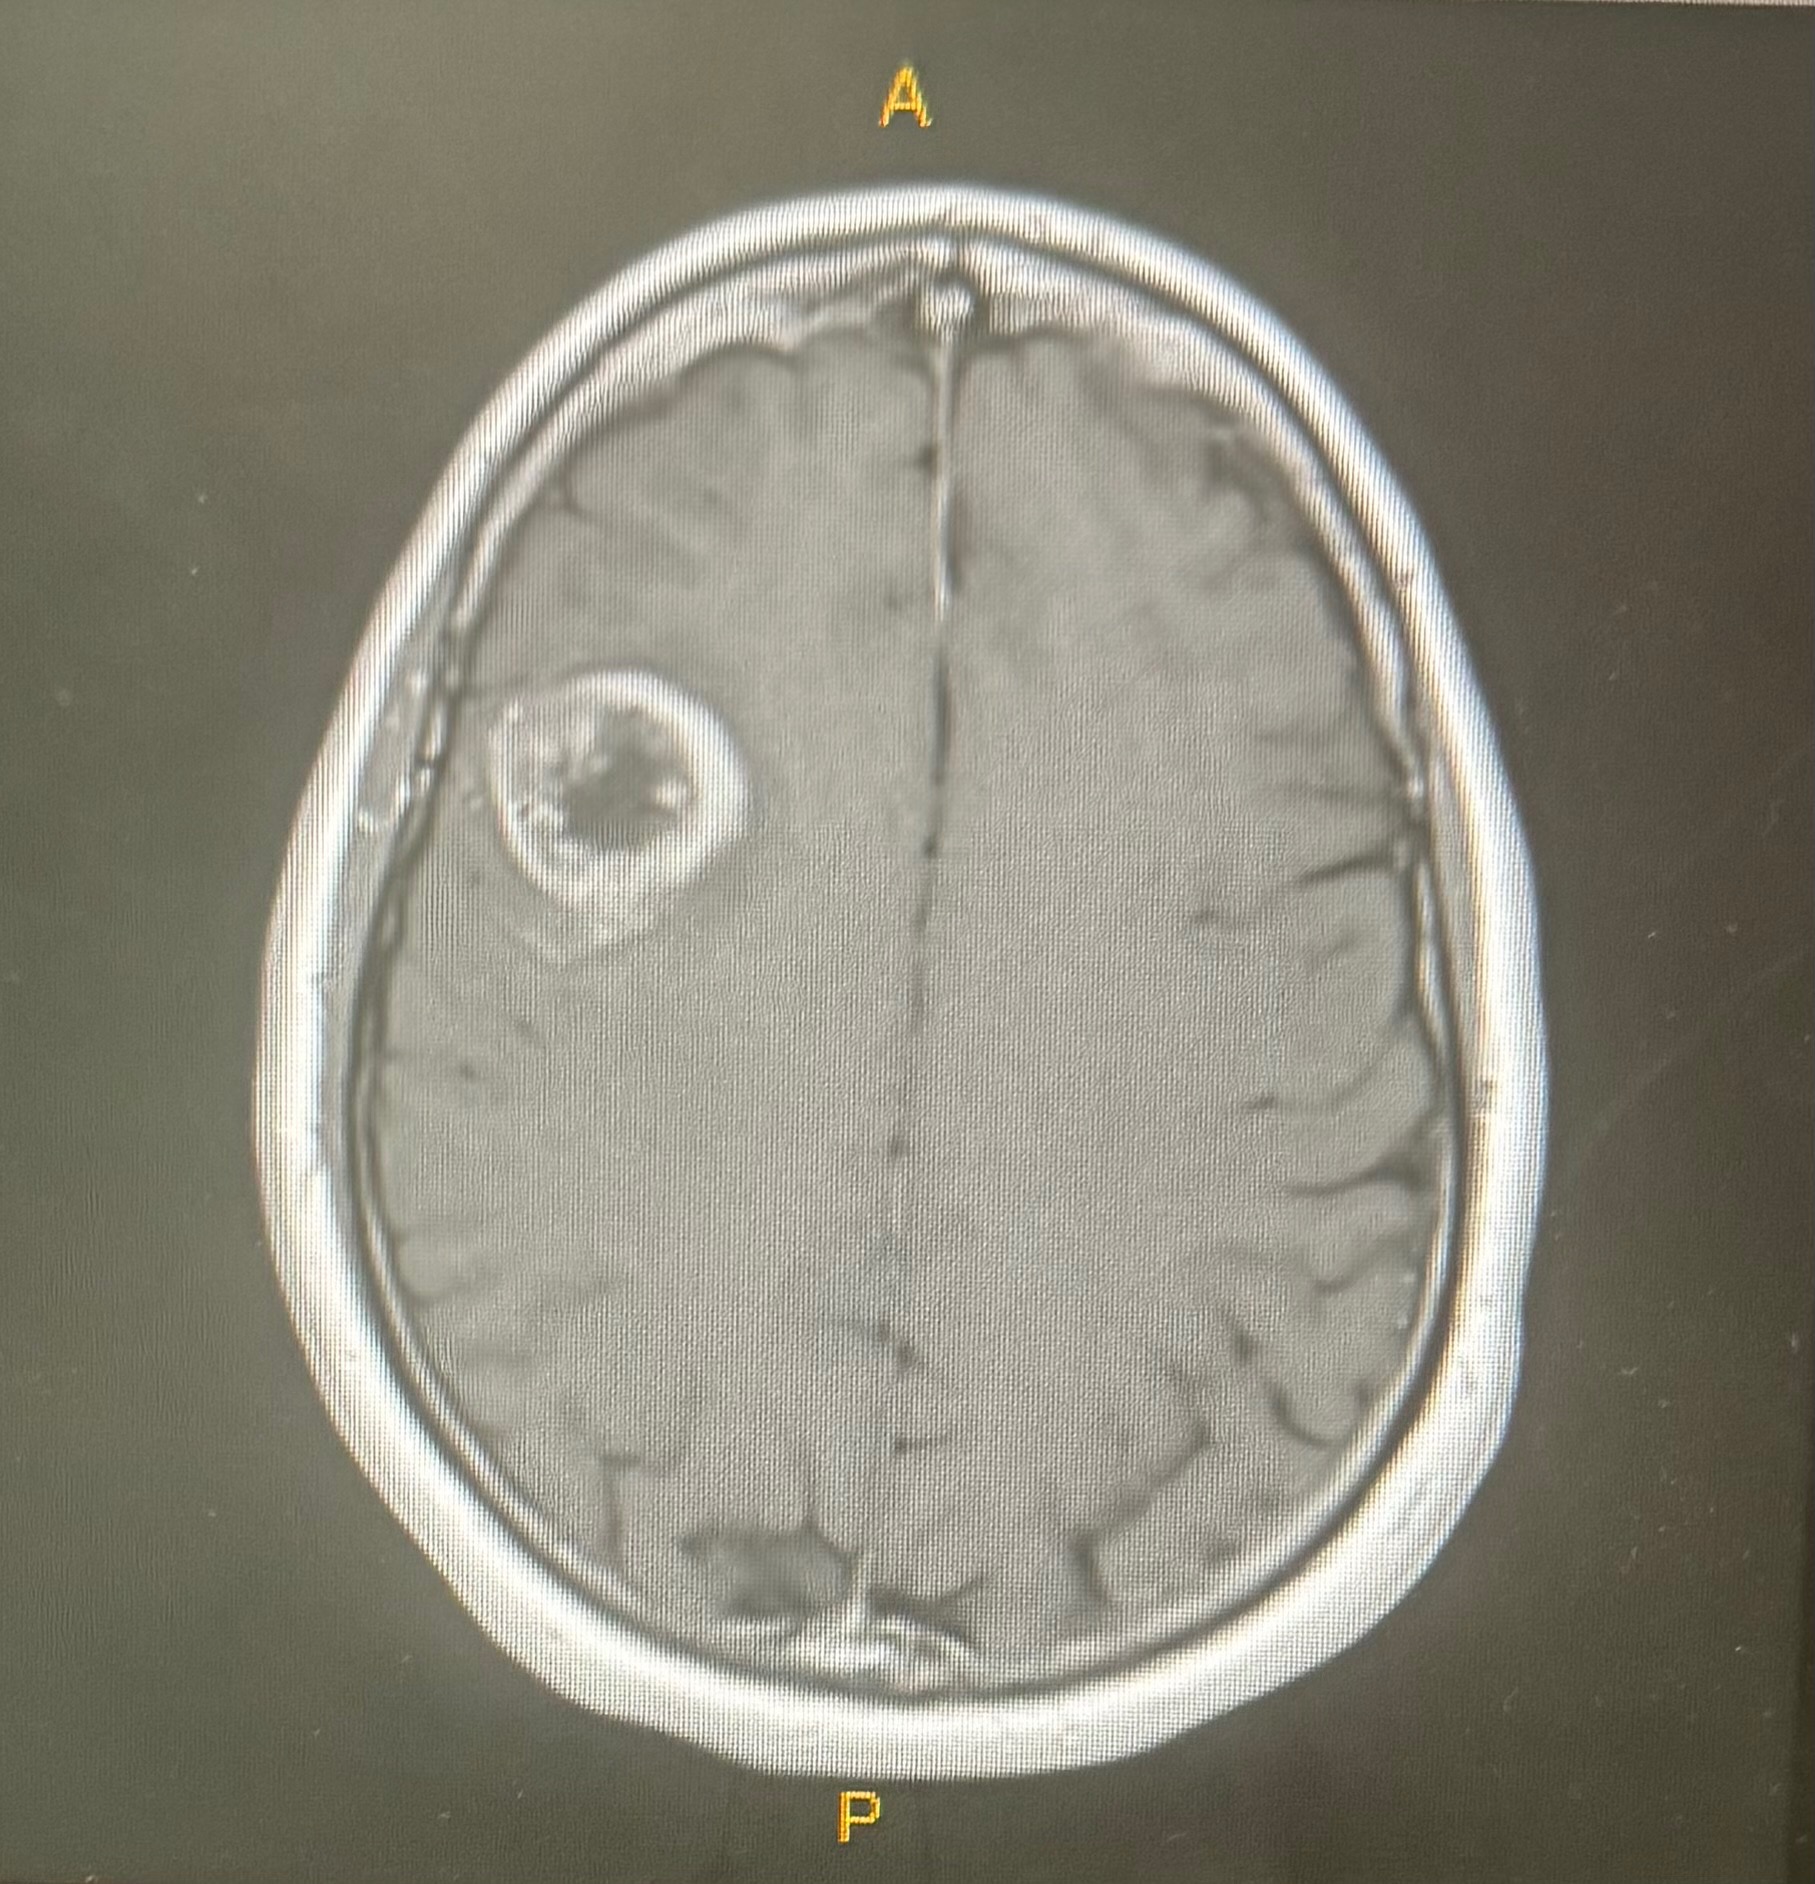

Today, I find myself once again in the ring vs. cancer. This time it is Glioblastoma, an aggressive brain cancer. It is completely unrelated to the preciosa breast cancer. Fun huh?! - 47 yrs young and I have developed 2 unrelated types of cancer. I have hope and faith in the power of healing, and I feel strong and ready for a good fight against this new challenge.

After a successful surgery in October to remove the tumor from my right frontal lobe, I will now continue with the standard treatment (radiation and chemotherapy-here we go again!) This time, the fight’s focus is to to stave off recurrence. To do that I am exploring Integrative oncology treatments along side the standard treatments including a promising and personalized peptide vaccine from the CeGat institute in Germany, as well as other therapies to support my immune system and overall well-being. These approaches offer real hope for extending both the quality and length of my life — but they come with high costs that are not covered by insurance.